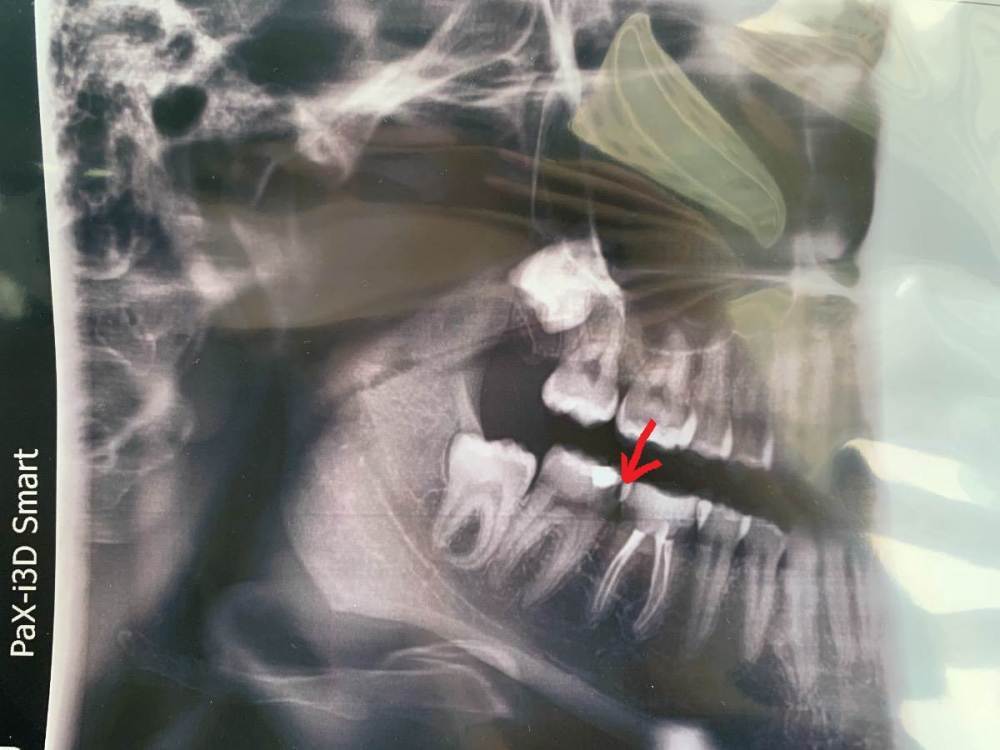

Mary189 Опубликовано 9 мая, 2022 Поделиться Опубликовано 9 мая, 2022 Здравствуйте уважаемые врачи. Уже на протяжении нескольких дней беспокоят периодические боли в области 7,6,5 зубов на нижней челюсти. Какой конкретно зуб непонятно, боль ноющая, давящая, не сильная, появляется и проходит в течении дня. При сжатии челюсти боли нет. Так же начала прорезываться восьмерка, судя по десне. Может ли она давать такие боли? Критична ли ситуация по снимку? Можно ли как то отложить поход к врачу? Ситуация осложнилась тем, что к стоматологу попасть в ближайшее время не смогу, попала неожиданно в больницу, возможно предстоит операция. Ссылка на комментарий

wladdX Опубликовано 9 мая, 2022 Поделиться Опубликовано 9 мая, 2022 Если судить по снимку и описанию, наиболее вероятный виновник зуб 47 (7-й внизу справа) Визит лучше не откладывать, может расшалиться "будь здоров" 1 1 Ссылка на комментарий